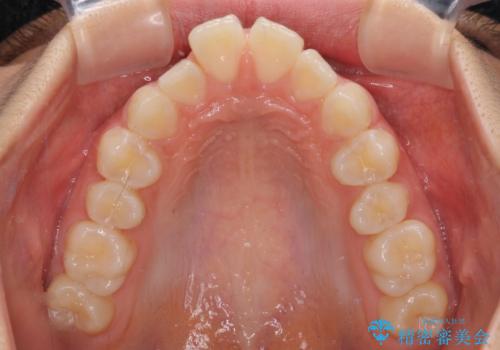

深い咬み合わせで前方に煽られた前歯 高校生のインビザライン矯正治療

- 前歯の隙間と前方に飛び出していることを気にして来院された患者様です。

奥歯の咬み合わせと深い咬み合わせを改善した後、隙間などをインビザラインで整えることとしました。

インビザラインをしっかりと装着したことはもちろん、高校生は歯の動きが早いため、非常に短期間で治療を終えることができました。